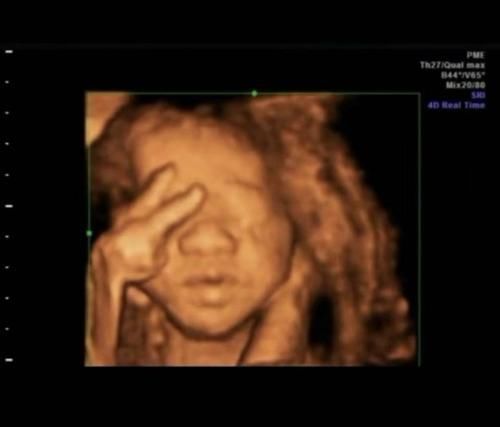

许多怀孕的母亲在进行4D拍摄时发布了自己的照片,发现婴儿的动作“奇妙”,有些会“食指”,有些在“笑”,并且婴儿在玩脐带。当然,这是正常现象。